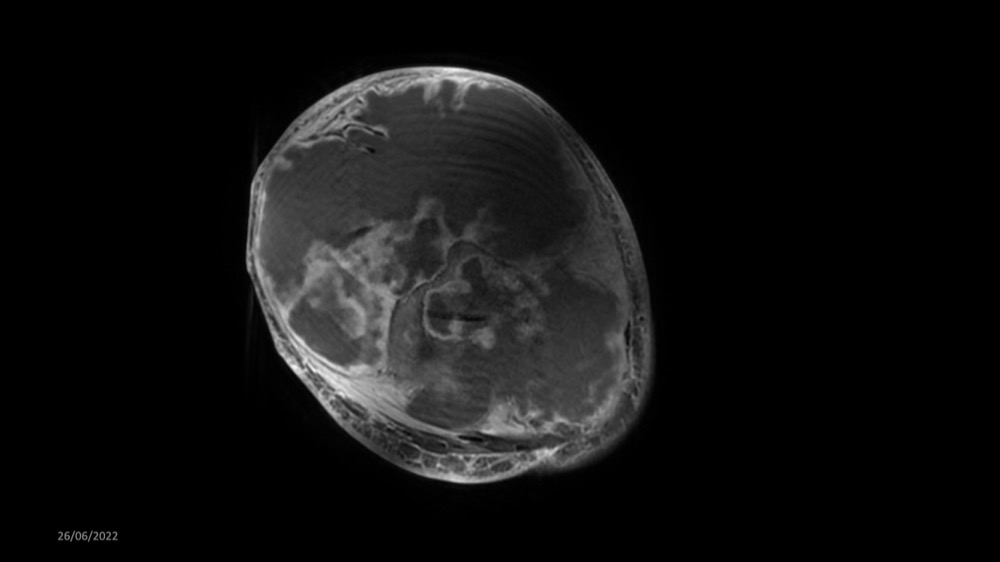

Reichert / Amar / Tordjman / Carlier 29/06/2022